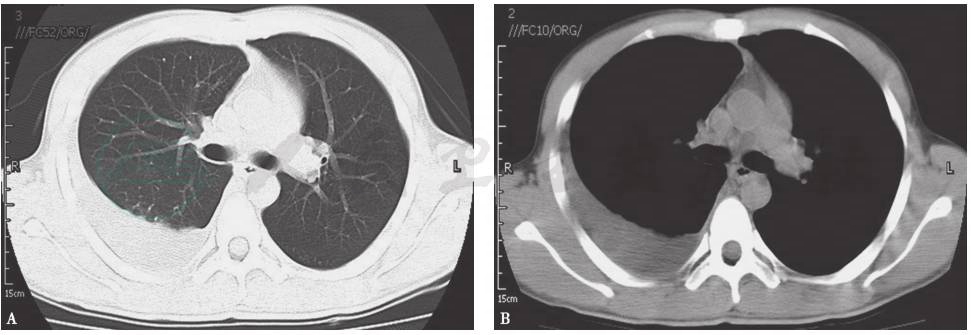

胸部CT:两肺门及纵隔内多个淋巴结肿大,斜裂胸膜区多发小结节,两肺间质纹理增多,双侧胸腔积液,右侧胸腔积液较前明显增多(图8)。

图8 胸部CT表现

引自:呼吸系统疑难病例诊疗辨析.第1版.ISBN:978-7-117-26415-0.主编: